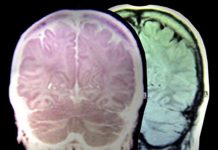

Εγκεφαλικό & κληρονομικότητα: Πώς θα μειώσετε τον κίνδυνο κατά 66%

Αν στην οικογένειά σας υπάρχει ιστορικό εγκεφαλικών επεισοδίων, ο καλύτερος τρόπος για να προστατευθείτε είναι η υιοθέτηση υγιεινού τρόπου ζωής, αναφέρουν οι επιστήμονες.

Μελέτη σε πάνω από 306.000...